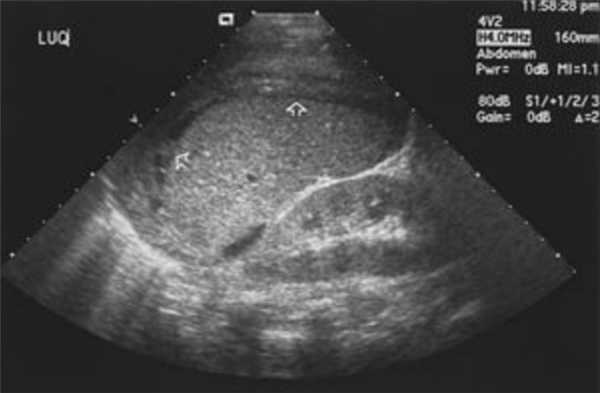

3.1. УЗИ желудка

3.2. УЗИ кишечника (эндоректальная ультрасонография)

УЗИ желудка — базовое обследование органа

Один из самых важных внутренних органов человека, принимающий участие в жизнедеятельности организма — желудок. УЗИ желудка - это самостоятельный и полноценный способ диагностики патологических изменений в органе. Благодаря доступности, информативности и безвредности этот метод обследования назначается очень часто. Как правило, он является отправной точкой для эндоскопии - более детального, но чрезвычайно неприятного метода обследования желудка.

Что показывает УЗИ желудка

Анатомическое расположение, содержимое и наличие газового пузыря в желудке значительно затрудняет визуализацию органа. Тем не менее, УЗИ - рациональный диагностический метод, поскольку позволяет оценить терминальные и выходные отделы, а поражения чаще всего сосредоточены именно в них.

На УЗИ желудка можно хорошо видны:

- малая и большая кривизны;

- часть тела желудка;

- привратниковая пещера;

- канал привратника;

- пилорический сфинктер — область перехода в двенадцатиперстную кишку;

- часть двенадцатиперстной кишки.

В ходе процедуры врач оценивает величину органа, его форму и размер, локализацию, толщину стенок, эхоструктуру, моторную функцию, а также наличие деформаций и инородных предметов.